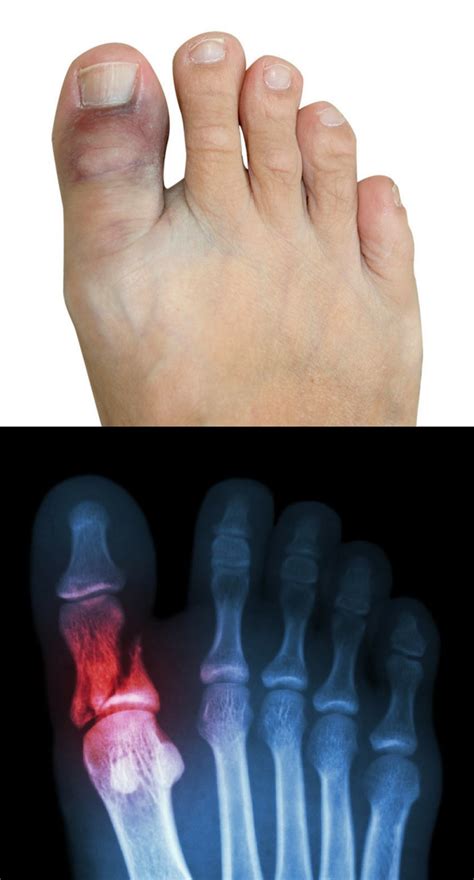

Stubbing your toe is one of the most common household accidents, but when the pain is intense, the swelling is immediate, and you cannot bear weight on your foot, you may be dealing with a broken big toe. Because the big toe plays a critical role in balance, walking, and propelling your body forward, an injury to this area can significantly disrupt your daily life. Understanding how to identify, treat, and recover from this injury is essential to ensuring that your foot heals properly and regains its full function.

Distinguishing between a badly stubbed toe and a fracture can sometimes be difficult because both present with pain and swelling. However, a broken big toe often involves more severe, localized symptoms. Recognizing these signs early is the first step toward effective management.

• Significant swelling or bruising that may spread to the surrounding foot area.

• Visible deformity, such as the toe pointing in an unnatural direction or appearing bent.

While some minor fractures might allow you to limp around, a major fracture of the big toe typically makes walking nearly impossible. If you suspect your toe is broken, it is best to err on the side of caution and consult a healthcare professional for an X-ray to confirm the diagnosis.